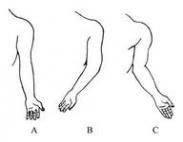

肘外翻

628健康网为您分享有关肘外翻的症状,肘外翻的治疗方法,肘外翻的预防知识,肘外翻的症状图片,肘外翻吃什么药,肘外翻怎么治...